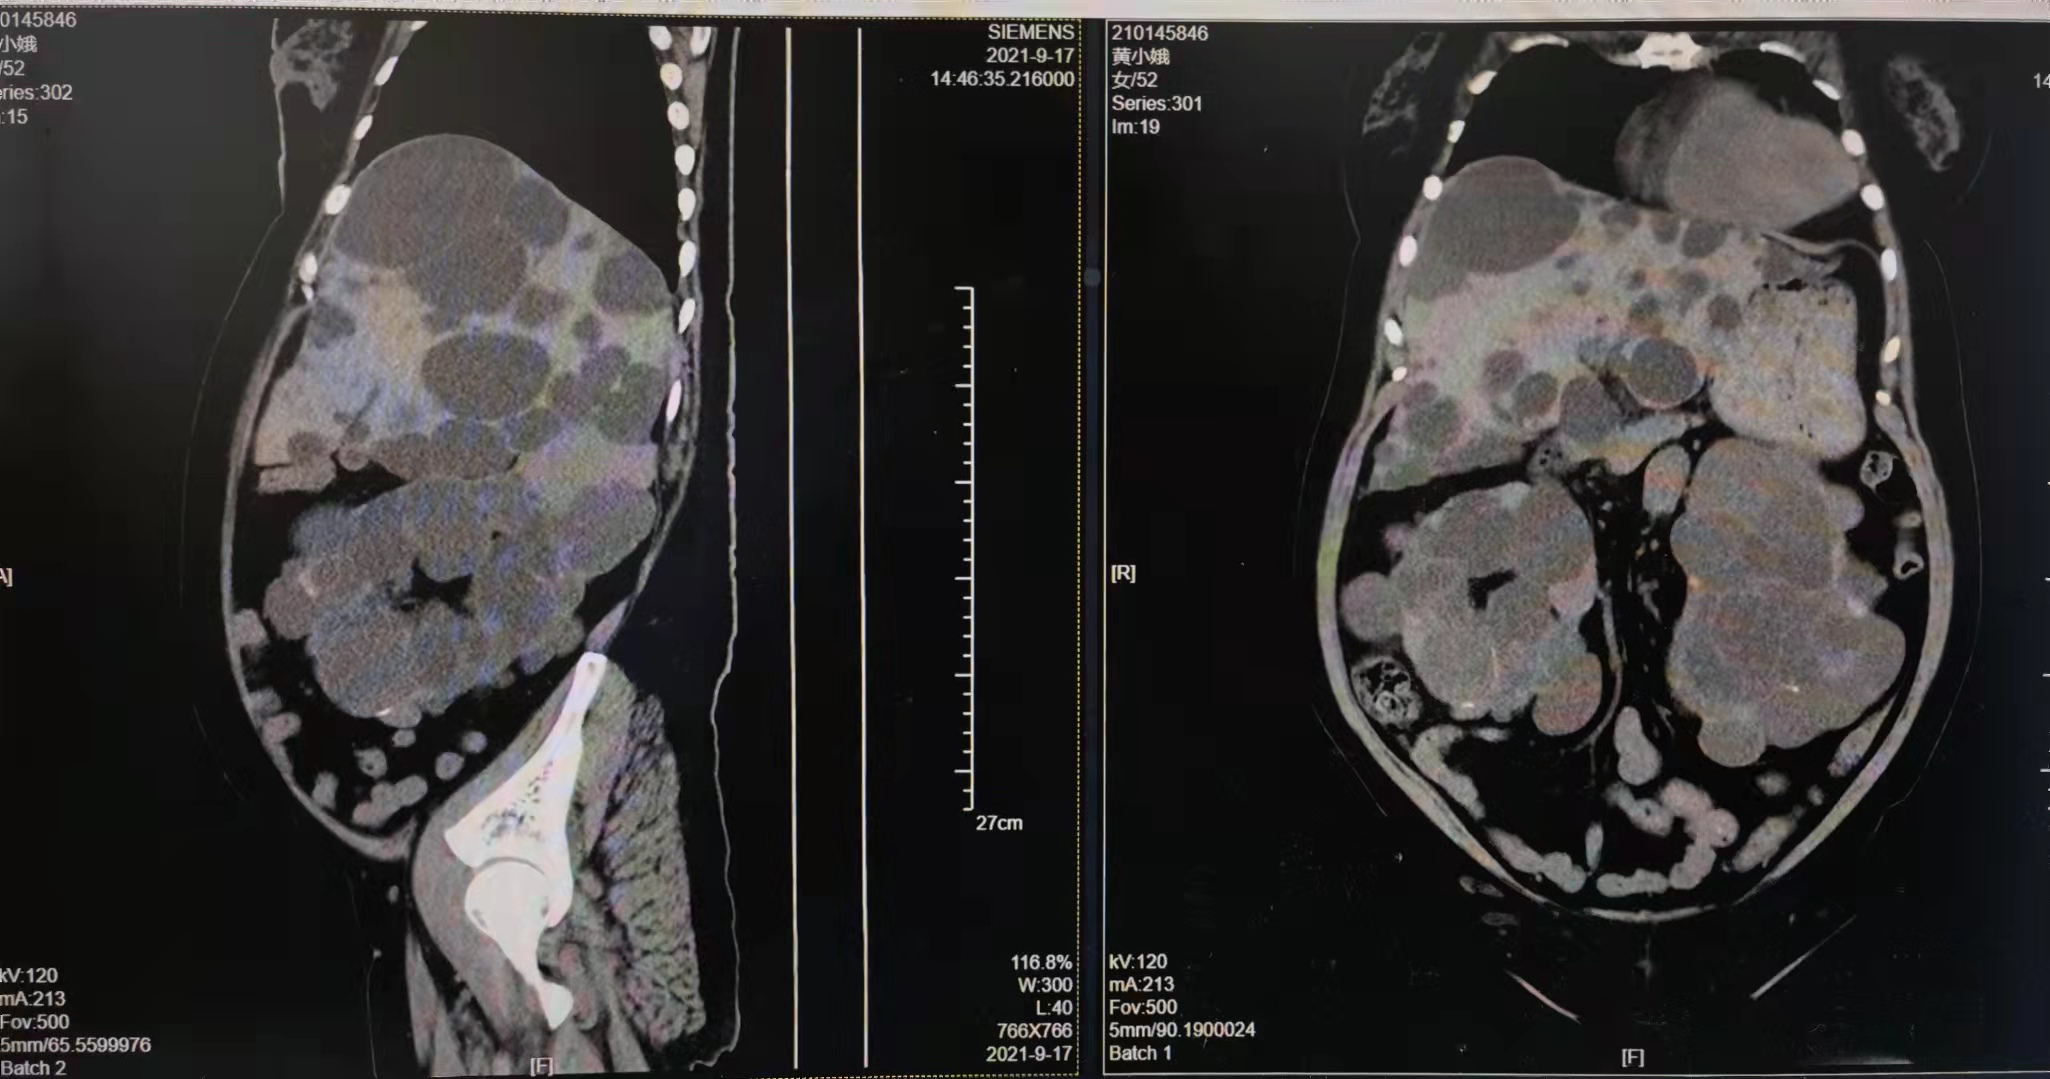

据悉,52岁的黄女士,因“不规则阴道流血2年”在今年9月初就诊于当地医院,行诊刮术后考虑子宫内膜癌。患者多囊肝、多囊肾10余年,并发尿毒症2年,规律透析1年多,因合并多囊肝、多囊肾手术难度大,当地医院建议上级医院就诊,最终患者通过多方途径咨询到湘雅名医薛敏教授对于妇科疑难杂症的诊疗经验和担当后,慕名至中南大学湘雅三医院妇科薛敏教授专家门诊请求手术治疗。

薛敏教授了解该患者病情后,将其优先收入院。经医院妇科团队仔细评估发现,患者肝脏达脐上一指水平,合并中度贫血、血小板减少,手术空间小、难度大、风险高。为此,医院在妇科邓新粮教授的组织下,于9月18日邀请肝胆胰外科、泌尿外科、肾内科、重症医学科、麻醉科、放射科、血透室、病理科进行MDT多学科会诊,细节决定成败,从腹腔镜开放式气腹孔的位置到每次透析的方式时间都制定了详细的诊疗计划。